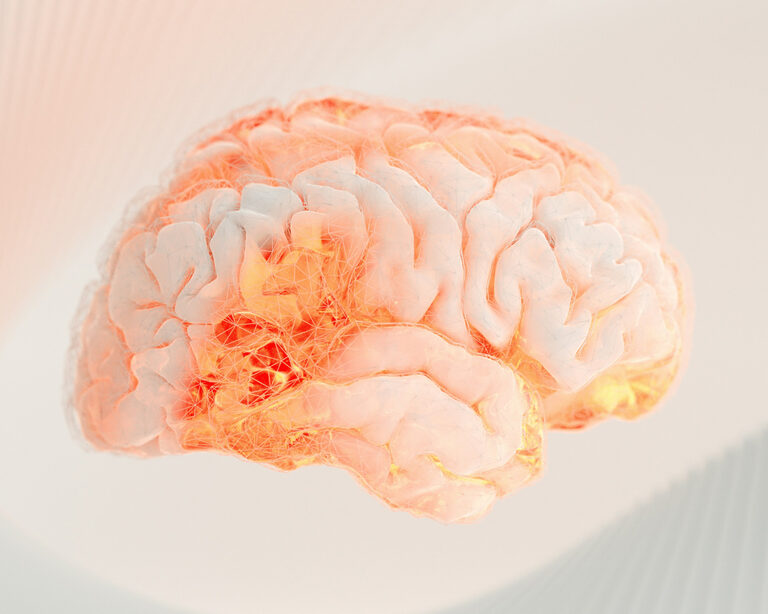

Спустя девять месяцев был проведен второй этап, в рамках которого все участники выполнили магнитно-резонансную томографию (МРТ) головного мозга и прошли комплексное нейропсихологическое тестирование. Было установлено, что у лиц, не имевших постоянных и надежных слушателей, когнитивный возраст в среднем был на четыре года больше по сравнению с теми, кто обладал устойчивой социальной поддержкой. Более того, у второй группы возрастное уменьшение объема мозга, связанное с атрофией, соответствовало лишь трем-четырем месяцам когнитивного старения.

- Когнитивная стимуляция. Процесс доверительного общения, формулирования мыслей и аргументации является сложной когнитивной задачей. Он активирует нейронные сети, ответственные за память, речь и исполнительные функции, способствуя поддержанию их функциональности. Как отмечают эксперты, взаимодействие с широким кругом людей, включая малознакомых, создает позитивный стресс, который стимулирует социальное обучение и поддерживает когнитивную гибкость.

- Снижение стресса и негативного воздействия депрессии. Возможность выговориться и получить эмоциональную поддержку является действенным буфером против хронического стресса. Длительный стресс, в свою очередь, связан с повышением уровня кортизола, который может оказывать повреждающее действие на структуры мозга, в частности на гиппокамп, играющий ключевую роль в памяти. Исследование выявило, что наличие поддержки способствует минимизации не только когнитивных, но и сердечно-сосудистых рисков, что косвенно благоприятно сказывается и на мозговом кровообращении.